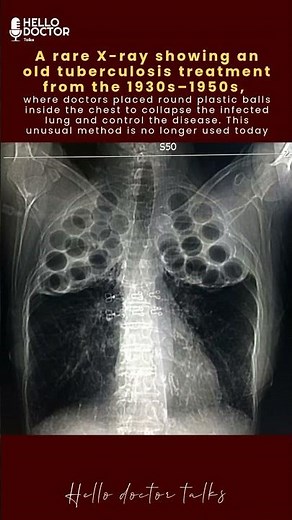

A rare X-ray showing an old tuberculosis treatment from the 19

…

已浏览 282.8万 次

1 个月前

YouTube

Hello Doctor Talks